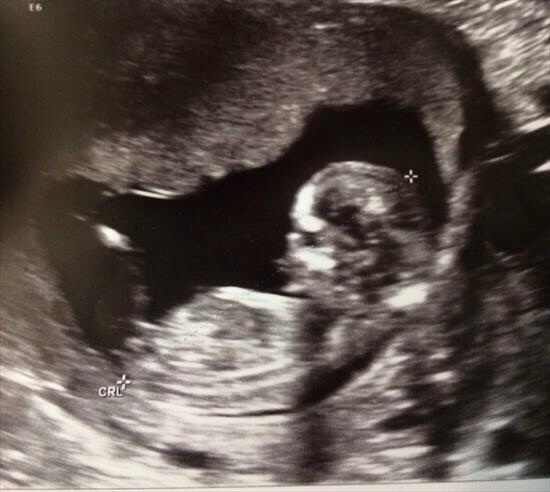

Baby is a bit too curled for my liking in both the shots that show any nub-action. My first thought was boy because of the end of the top nub. But given the curled baby, I wonder if I am seeing that because of how the spine is. I can't say I am leaning strongly either way. Sorry!

I am going to say boy

50/50 based on curve of spine xx

boy

Boy x